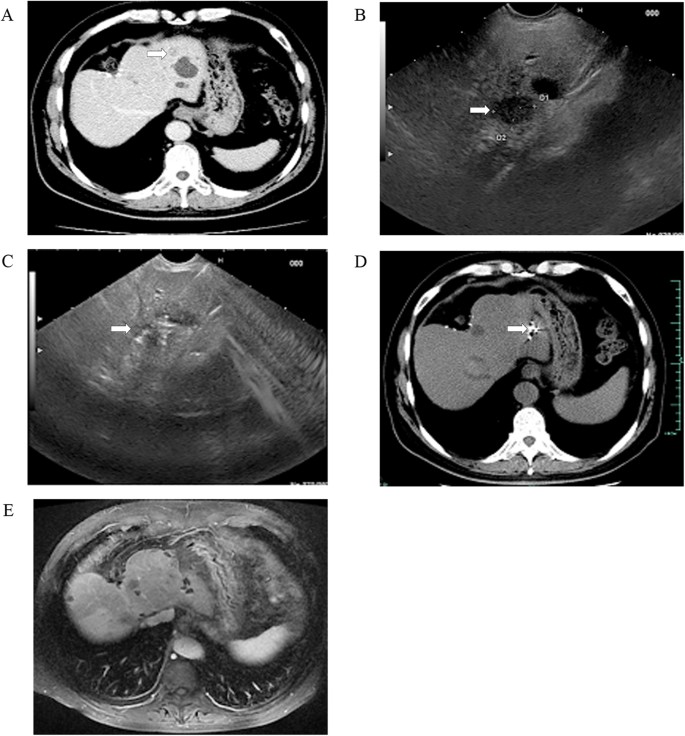

Overall, 26 patients were enrolled in this study, including 17 men and 9 women, aged 31–75 years. The basic characteristic of included patients was summarized in Table 1. The aetiologies of the hepatic tumors were chronic hepatitis (n = 6), liver cirrhosis (n = 11), and primary gastrointestinal malignancy (n = 9). Twenty-one patients had a single left-sided liver tumor, and 5 patients had more than one liver tumor with major disease located in the left lobe but multiple tumors in the right lobe. Liver tumors were occurred in left liver shadowed by gastrointestinal (GI) gas (n = 12; Fig. 1), resection margin (n = 7; Fig. 2), caudate lobe (n = 3; Fig. 3), significantly atrophic left lobe (n = 2), and remarkable abdominal skin scar (n = 2). All tumors were not detectable or poorly visualised on percutaneous ultrasound scan because of the above reason. In addition, a systematic review by searching from PubMed up to August 2016 was performed. The summary of 11 studies of ethanol ablation and 125I brachytherapy of the hepatocellular carcinoma was presented in Table 2 12,13,14,15,16,17 and Table 3 9,18,19,20,21.

EUS-guided iodine-125 brachytherapy for postoperative liver metastasis of cholangiocarcinoma.

(A) presence of a 1.3-cm, low-density liver mass located in the left lobe on CT scan (white arrows). US image failed to show the lesions due to the gas ahead; (B) identification of a 1.5 cm × 1.3 cm low-echodensity mass on EUS (white arrows); (C) EUS-guided implantation of iodine-125 particles (white arrows); (D) obvious downsizing of the liver disease on follow-up CT scan at 1 months (white arrows); and (E) disappearance of the liver disease on follow-up MRI scan taken after 12 months.

All patients were followed up for 1–2.5 years as scheduled. At 12 months after treatment, 12 of 13 (92.3%) patients achieved complete tumor response in iodine-125 particle implantation (Fig. 1) while 3 of 10 (30%) in anhydrous ethanol ablation (Fig. 3 and Table 4). Residual tumor was detected in 8 patients after anhydrous ethanol ablation (n = 2) or iodine-125 particle implantation (n = 6); these patients were further treated with second-look EUS-guided interventional treatment (n = 5) and radiotherapy (n = 2) and surgical resection (n = 1). Complete response was achieved after again EUS-guided treatment in 3 of 5 patients, whereas the remaining 2 patients required surgical resection but only one succeed. Recurrence was observed in 2 patients at 1 year after anhydrous ethanol ablation. No clinically significant late-onset complications occurred.